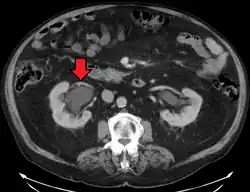

CT scan of bilateral hydronephrosis due to a bladder cancer -

Massive hydronephrosis as marked by the arrow. -

Stone causing hydronephrosis[13]